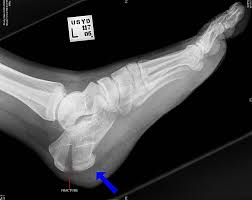

Il quadro radiografico risulta fondamentale per diagnosticare qualsiasi tipo di frattura. Nel caso delle fratture di Calcagno, la gravità del trauma viene valutato tramite la misurazione dell’angolo tuberositario di Bohler, il quale indica il rapporto articolare tra calcagno e astragalo.

In un soggetto sano, l’angolo di Bohler è di 30 gradi, nelle fratture di primo grado può essere ridotto a 10-15 gradi, nelle fratture di secondo grado l’angolo è prossimo allo 0, e nelle fratture di terzo grado l’risulta addirittura invertito.